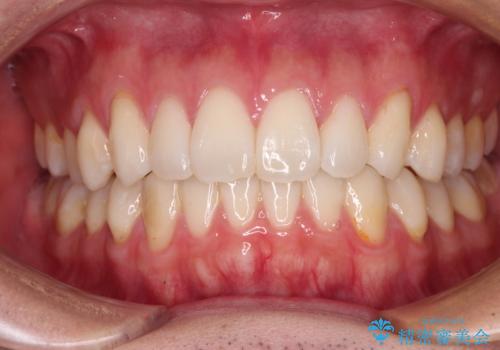

少しでも口元を閉じやすく インビザラインによる前突の解消

- 全体的なデコボコと、前歯の前に出ている感じを気にして来院された患者様です。

患者様と相談の上、非抜歯にてインビザラインを用いて矯正治療を行うこととし、IPR(歯と歯の間)並びに歯列全体の後方移動により口元の突出感の改善することとしました。

お仕事が忙しい方で、装着時間が不足したり、定期的な通院ができなかったりと、自己管理が重要なインビザラインによる矯正治療が長期化する要因が重なり、5年ほどの期間を要しました。